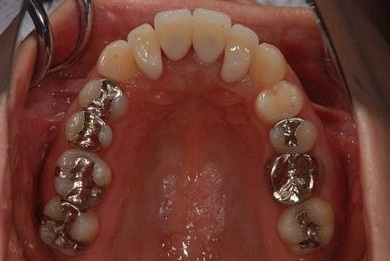

治療後

• 治療後